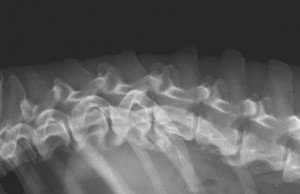

Espondilose ou espondilose deformante tem sido definida como um colar prediscal de tecido ósseo neo-formado que liga a córtex ventral e/ou lateral de corpos vertebrais adjacentes (Thrall, 2002). A espondilose é mais comum em vértebras torácicas, lombares e lombo-sacrais de cães machos idosos e de meia idade. É uma lesão não inflamatória e o osso neo-formado pode variar de um pequeno osteófito até uma ponte completa entre vértebras adjacentes. A espondilose pode aparecer adjacente a um disco intervertebral degenerado, protuído ou normal e pode estar associada a um sítio de instabilidade espinhal, mas frequentemente sua etiologia é idiopática (Morgan 1967 e 1988, Wright 1982).

São três as doenças que podem ocorrer no disco intervertebral: ruptura do disco, prolapso do disco e herniação do disco intervertebral (por protusão ou extrusão deste). Os sinais clínicos das doenças dos discos intervertebrais, que causam compressão medular, são usualmente neurológicos. Animais afetados podem apresentar dor, com ou sem paresia ou paralisia. A doença é mais comum em raças condrodistróficas, como o Teckel, Beagle, Cocker e Pequinês. O sinal radiográfico mais de doença do disco intervertebral é a mineralização ou calcificação deste. Outros sinais incluem a diminuição de espaço intervertebral e esclerose, diminuição do tamanho ou formato do forame intervertebral, aumento de radiopacidade do forame intervertebral e esclerose das epífises articulares dos corpos vertebrais adjacentes ao disco alterado (Owens e Biery, 1999).

A radiografia convencional é o método primário de escolha no diagnóstico de alterações da coluna vertebral, porém apresenta limites na avaliação diagnóstica em alguns quadros de discopatias, uma vez que a densidade da lesão mineralizada pode não ser suficiente para revelá-la, tornando limitada a avaliação do espaço intervertebral que se apresenta reduzido nos processos de deslocamento do disco intervertebral (Hecht ET AL, 2009). Mielografia, tomografia computadorizada e ressonância magnética são exames complementares considerados no diagnóstico de discopatias.